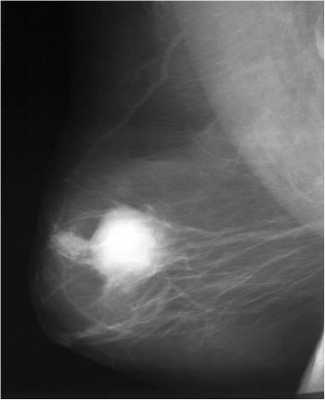

Неоадъюватная (предоперационная) терапия

Эффект неоадъювантного лечения ДО (слева) и ПОСЛЕ (справа)